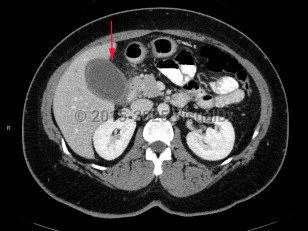

Acute cholecystitis is a surgical emergency of the biliary tract that can be life-threatening if appropriate treatment is not initiated promptly. Acute cholecystitis is characterized by gallbladder wall inflammation. Patients classically present with right upper quadrant (RUQ) abdominal pain, fever, and leukocytosis. Acute cholecystitis is further categorized by the presence of gallstones as calculous or acalculous.

Acute calculous cholecystitis occurs when a gallstone blocks the cystic duct, impairing gallbladder drainage. Temporary obstruction can cause biliary colic. Sustained obstruction can result in gallbladder dilation, wall inflammation, subsequent wall thickening, and pericholecystic fluid accumulation.